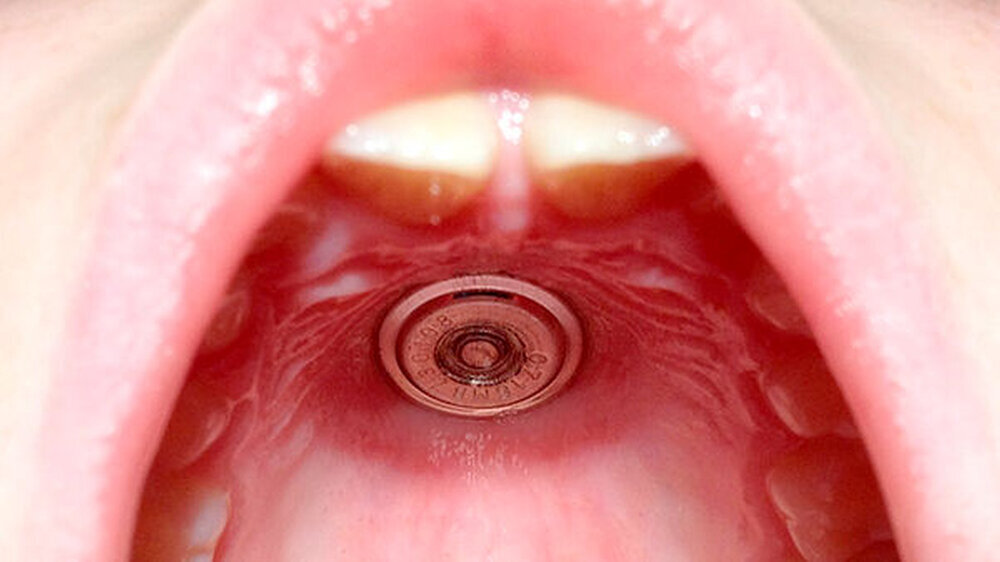

Die klinische Untersuchung zeigte, dass der Boden der Batterie fest mit der Schleimhaut des Gaumens (Abbildung 1) verbunden war. Es erfolgte das vorsichtige Ablösen des Batteriebodens mit einer feinen chirurgischen Pinzette. Die anschließende Kontrolle - entfernter Batterieboden und restliche Bestandteile (vom Vater mitgebracht) - zeigte, dass die Batterie vollständig war, so dass sich kein Anhalt auf eine akzidentelle Aspiration von Batteriebestandteilen ergab.

Im Bereich der oralen Schleimhaut war lediglich eine lokale, sich auf die direkte Kontaktfläche der Batterie beschränkte Schleimhautreizung mit Rötung bei intakter Schleimhautoberfläche erkennbar.